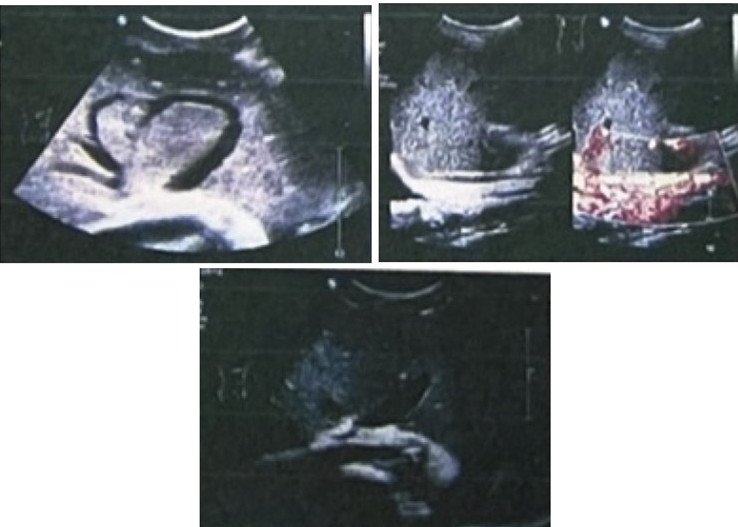

图1 肝静脉和下腔静脉彩色超声所见

影像学检查可为BCS提供有价值的信息,对无法确诊,但又不能排除本病的患者,我们应行彩超筛选。彩色多普勒既能观察病变部位的形态、结构,又能了解血流动力学改变,可明确判断血管阻塞的部位、程度、范围及侧支循环情况,并可对病情分型,适合对患者作筛选检查,亦可作为术后随访和疗效判断的主要手段。